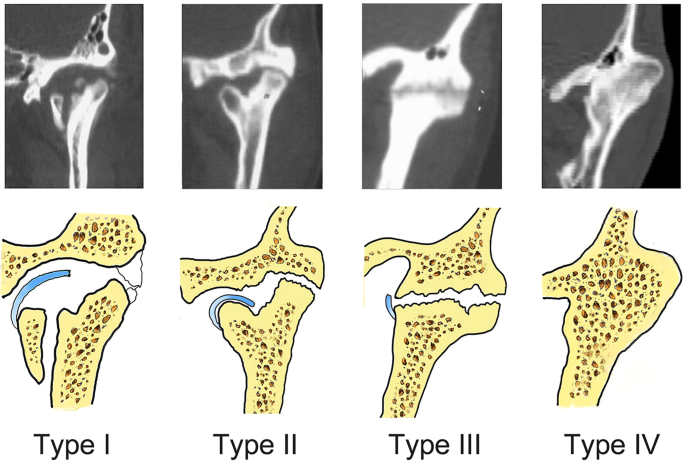

Computed tomography images and representations of the four types of temporomandibular joint ankylosis. Type I is nonbony ankylosis of the joint, with the fossa and condyle clearly seen but with scattered callus. Type II is lateral bony ankylosis of the joint, with bony fusion on the lateral side of the joint. The medially displaced condyle, residual disc, and fossa form a pseudarthrosis. Type III is complete bony ankylosis of the entire joint with a radiolucent line inside the fusion area but no recognizable condyle and fossa. Type IV is extensive bony ankylosis, with complete disappearance of the joint and with no radiolucent line.

Considering the change in joint space and the radiolucent zone on coronal CT, all ankylosed joints were categorized into one of four types (Fig. 1): type I, non-bony ankylosis of the joint with an almost-normal joint space and without bony fusion or a radiolucent line; type II, lateral bony ankylosis of the joint with lateral bony fusion and a radiolucent line inside the fusion area (medially discernible joint space coexisting with a displaced condyle); type III, complete bony ankylosis of the whole joint with a radiolucent zone inside the fusion mass but no clearly defined joint space; and type IV, extensive bony ankylosis with no clear definition of the joint or no radiolucent zone. When a patient with bilateral TMJ ankylosis had a different type of ankylosis on each side, the classification was based on the more critical side. All ankylosed joints were categorized by two surgeons who were members of the Department of Oral and Maxillofacial Surgery and were engaged in TMJ ankylosis research for >5 years. Any difference in opinion between the two surgeons was resolved by a third surgeon. The CT images were evaluated by three surgeons in a single-blind test.